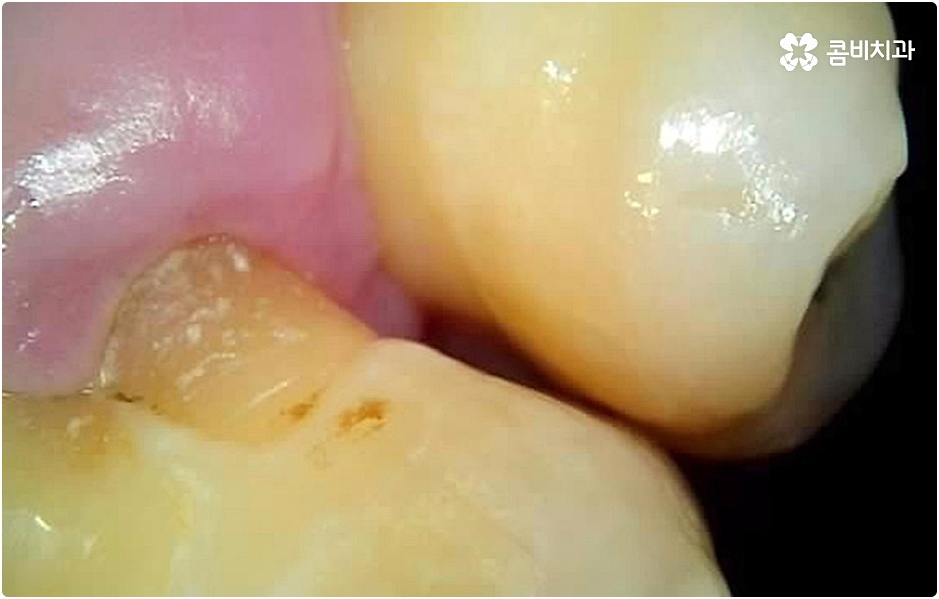

이러한 치아를 상실하게 된다면 우리가 생활하면서 느끼게 되는 불편함이 매우 클 거예요. 보통 치아 상실의 주된 원인이 노화 또는 치주 질환이기 때문에 중장년층 이상 노년층에서 많이 발생한다고 생각하실 수 있으나 젊은 나이에도 얼마든지 구강 질환 또는 사고 등으로 치아 상실을 경험할 수 있으며 특히 액티비티 활동을 활발하게 즐기는 20대라면 자칫 치아가 심하게 부러지거나 크게 깨지면서 결국 해당 자연 치아를 살릴 수 없게 되는 상황에 이를 수도 있기 때문에 주의하실 필요가 있어요.

그러나 나이가 젊다고 해도 만약 치아를 상실한 원인이 심각한 구강 질환으로 인한 것이거나 치아를 잃고 나서 오랜 시간 방치를 하였거나 평상시에 당뇨 또는 고혈압 등을 앓고 있었다면 환자분의 잇몸뼈 건강이 양호하지 않을 수 있으며 그런 경우에는 즉시 임플란트 시술을 받을 수 없고 먼저 뼈이식 과정을 통해서 잇몸뼈를 보충해 준 다음 20대임플란트 식립을 진행하는 것이 정확도와 지속성을 높여주는 방법이라고 할 수 있어요.

그러나 언급했던 것처럼 잇몸뼈 상태에 대해서 먼저 체크해 봐야 하기 때문에 누구나 받을 수 있는 치료 과정은 아니라는 점을 분명히 알아두실 필요가 있습니다. 이렇게 잇몸뼈를 보충해야 하는 상황 뿐 아니라 충치 또는 치주 질환을 먼저 깨끗하게 치료해야 하는 상황, 상악동까지의 거리가 너무 짧아서 거상술을 통해 혹시 모를 천공과 염증을 방지해야 하는 상황 등 여러 가지 선치료가 필요한 케이스들이 있을 수 있기 때문에 먼저 환자분들의 상황을 자세하게 파악하기 위해서 꼼꼼한 검진을 해 볼 필요가 있으므로 3D CT 등 정밀 검진 장비 보유 여부가 필수적이라고 말씀드린 거예요.

그러나 치아가 빠진 후부터 잇몸뼈는 수축을 하기 시작하기 때문에 오랜 기간 그대로 방치를 하게 되면 잇몸이 내려앉아 주변 치아가 쓰러지고 치열이 흩뜨러지며 악관절까지 좋지 않은 영향을 받게 되는 등 구강 내부적으로 문제가 더 커질 수 있으며, 치아가 크게 부러진 뒤 치근이 일부 남아 있는 상황이라고 하더라도 기능을 전혀 하지 못하여 주변 치아와 잇몸에 지속적인 부담을 주고 있거나 해당 부위를 통해 감염이 일어날 가능성이 높다면 이를 발치하고 빠르게 기능적 심미적 대체를 해 줄 필요가 있으니 될 수 있는대로 바로 치과로 내원하셔서 검진부터 꼼꼼하게 받아보시고 그에 적합한 치료를 받으시길 권유드리고 있어요.